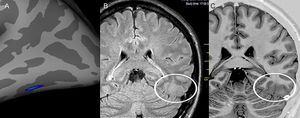

Example of a patient with a presumed epileptogenic zone in the left frontotemporal region (patient 7) that was concordant with three quantitative measures. The results of postprocessing of T2 relaxometry maps by Statistic Parametric Mapping (SPM12) software (a: coronal plane) and mean diffusion maps (b: sagittal plane), as well as cortical thickness by FreeSurfer (c: quadrature decoder [QDEC]), showing abnormalities notably in the left frontal lobe.

RESULTSStatistical analysis and multimodal postprocessingA compilation of the results of quantitative analysis through individualized postprocessing in the 46 patients is given in Table 2. A close correlation (even lobe) between the abnormal findings in at least two of these quantitative measures, which also corresponded to the electroclinical origin of the seizures, was identified in five patients in this group (5/31, 16.1%) (Figure 1).